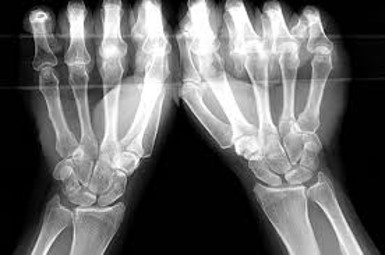

An x-ray can be beneficial to review bony alignment, and to check for any abnormalities such as widened gaps between carpal bones and dorsal or volar intercalated segment instability (DISI/VISI).

Photo source: www.europepmc.org